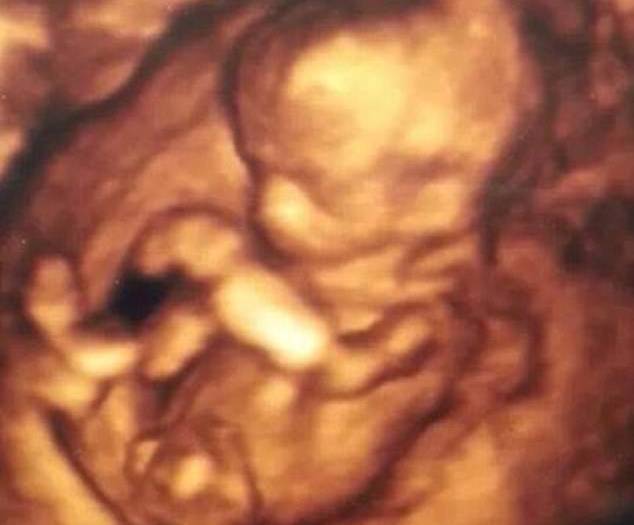

A dispetto di tutti i pareri medici Angela Morales, bimba affetta da anencefalia, ha compiuto 1 anno.

Bimba che non aveva speranze per i medici ha già compiuto 1 anno (FOTO & VIDEO)